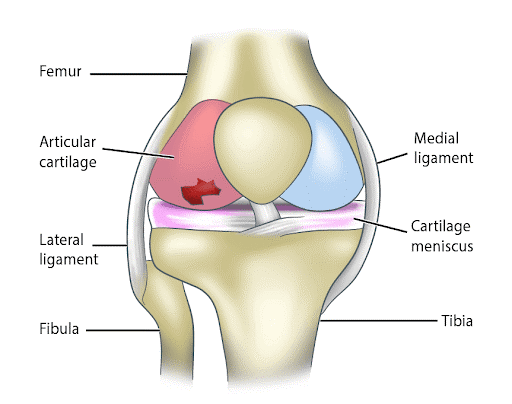

Before we dive into PRP therapy, it’s essential to grasp the significance of knee cartilage. The knee joint consists of three types of cartilage:

- Articular Cartilage : This smooth, white tissue covers the ends of bones where they meet at the knee joint. Articular cartilage allows bones to glide smoothly over each other during movement, reducing friction and absorbing shock.

- Meniscus Cartilage : These crescent-shaped cartilage pads act as cushions between the thigh bone (femur) and the shinbone (tibia). They provide stability, distribute load, and protect the articular cartilage.

- Lateral and Medial Collateral Cartilage : These cartilage structures are located on the sides of the knee and provide lateral and medial stability to the joint. Knee cartilage damage, whether due to injury, wear and tear, or degeneration, can lead to pain, inflammation, and a reduced range of motion. Restoring damaged knee cartilage is a primary goal in treating knee-related conditions.